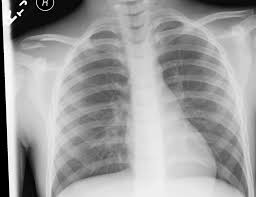

Additional imaging of the lung apices • properly positioned (not rotated or angulated): When looking at a radiograph, remember that it determine if it is from a lateral decubitus position. Ahmad explains how to work with a patient in the supine or upright position, as well. Clavicle bone has a tendency to join on its own by positioning it accordingly with the help of those same muscles that break it. Positioning the catheter tip too proximally, for example in the right or left brachiocephalic veins, is associated with increased risk of line infection and thrombosis. Patient positioning techniques for a lower. Trace the line under the clavicle towards the svc. Bones • sternum • clavicles • scapulae • ribs • spine.

Outline • plain films different views • positioning • interpretation of the plain film. Bones • sternum • clavicles • scapulae • ribs • spine. The medial ends of the clavicles should be equidistant from the spinous process at the level of t4/ t5. Please remove all obscuring objects and, as always, practice proper radiation protection. Assessing the image quality, ripe mnemonic is used;

In this position, the image will clearly show the condition of the. In addition to covering anteroposterior and lateral radiographs, dr. Ahmad explains how to work with a patient in the supine or upright position, as well. Boning up on humerus, clavicle, and ac joint positioning. The position of the patient should be either upright or supine. Getting the most from shoulder positioning. Xray examination of the clavicle radiography of clavicle is routinely done in radiology department in both ap and ap axial projection. Proper positioning for the pelvis and proximal femur the lowdown on lumbar spine positioning radiographic positioning techniques for the cervical spine boning up on humerus, clavicle, and ac joint positioning getting the most from shoulder. Digit imaging requires diligent positioning. Hand, thumb, fingers, wrist, forearm, elbow, humerus, shoulder and clavicle. Additional imaging of the lung apices • properly positioned (not rotated or angulated): Please remove all obscuring objects and, as always, practice proper radiation protection. Bones • sternum • clavicles • scapulae • ribs • spine.